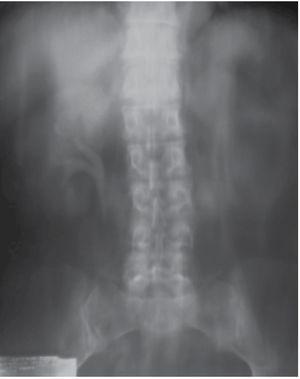

Ante este hallazgo se realizó urografía excretora, en la cual se observó en la fase de eliminación a los 30 minutos defecto de llenado en cáliz superior, sin dilatación de sistemas colectores del lado derecho. En el izquierdo no se aprecia captación de medio de contraste, incluso a los 60 minutos (Figura 1).

Figura 1. Urograma excretor en fase de vaciamiento, donde se observa defecto de llenado en cáliz superior y ausencia de captación del medio de contraste del riñón izquierdo.